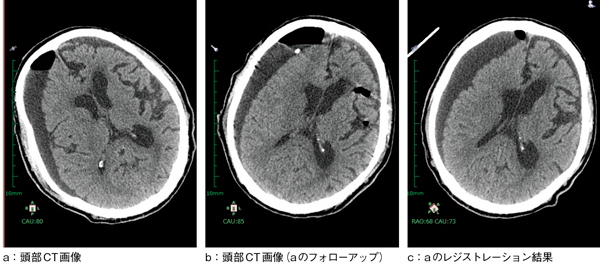

図1 ボリュームベースの位置合わせ(レジストレーション)

a,b:それぞれ別の日に撮影された頭部CT(再構成なし)。体位が異なるので,似たスライスを選んでも描出が微妙に異なる。

c:aと同じシリーズを,bに合わせて位置合わせした結果。MPRと回転によって比較読影は容易になり,硬膜下血腫のわずかな変化も検出しやすい。